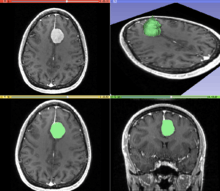

A T1 weighted MR image of the brain of a patient with a meningioma after injection of a MRI contrast agent (top left), and the same image with the result of an interactive segmentation overlaid in green (3D model of the segmentation on the top right, axial and coronal views at the bottom).

Segmentation is the process of partitioning an image into different segments. In medical imaging, these segments often correspond to different tissue classes, organs, pathologies, or other biologically relevant structures.[1] Medical image segmentation is made difficult by low contrast, noise, and other imaging ambiguities. Although there are many computer vision techniques for image segmentation, some have been adapted specifically for medical image computing. Below is a sampling of techniques within this field; the implementation relies on the expertise that clinicians can provide.